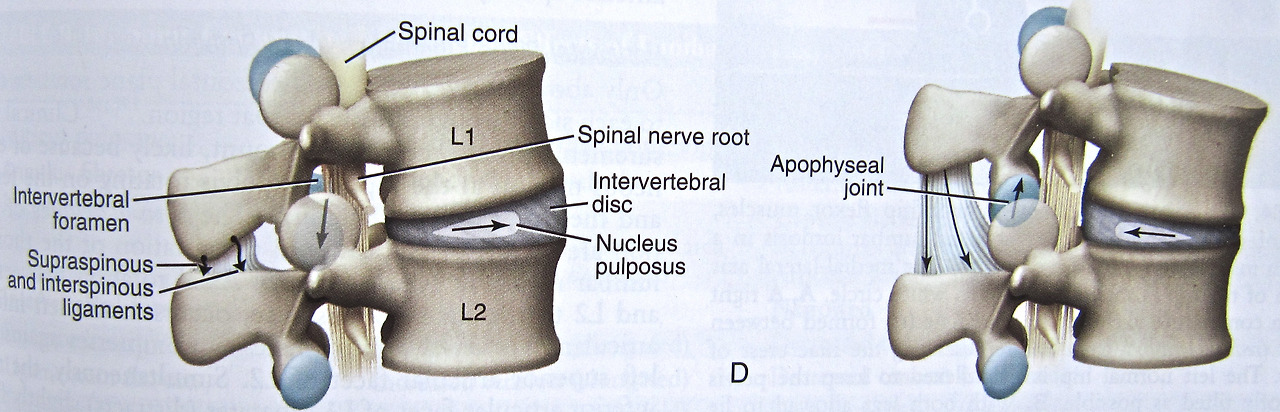

추간판탈출증은 우리가 흔히 알고 있는 디스크라고 불리는 척추 질환 중 하나입니다. 척추뼈와 척추뼈 사이에는 추간판(디스크)가 있으며, 이 디스크가 여러 원인으로 인해 손상을 입게 되면, 추간판 내부에 수핵이 탈출하게 되어 그 주변에 있는 척추신경이 압박되어 통증이 발생하는 신경학적 이상 증세입니다. 갑자기 무거운 물건을 들어 올리는 등 다양한 원인들 중 사고로 인한 급성 허리디스크, 체형의 변형, 노화로 인한 수핵 수분의 감소, 잘못된 자세가 지속되면 발생하는 피로나 스트레스로 인한 만성 허리디스크가 있습니다. 이러한 허리디스크는 요추(lumbar)에서 발생하며, 특히, 체중의 부하가 가장 높은 요추 4번과 5번(L4-5), 혹은 요추 5번과 천추 1번(L5-S1)에서 주로 발생한다고 알려져 있습니다.

요추의 해부학적 구조는 다음과 같습니다. 우선, 요추는 제1요추에서 제5요추로 구성되어있습니다. 각 요추들 사이에는 추간판이 있으며, 요추 사이에서 발생하는 충격을 흡수하는 역할을 하고 있습니다.

추간판은 크게 외부의 섬유 조직인 섬유륜과 내부의 젤리 형태의 수핵으로 구성되고 있습니다. 이 수핵이 디스크라고 불리며, 디스크는 스프링처럼 쿠션 역활을 하면서 충격을 완화시킬 뿐만 아니라, 척추 뼈가 밀리지 않게 하고 뼈들이 서로 부딪히지 않도록 보호하게 됩니다.